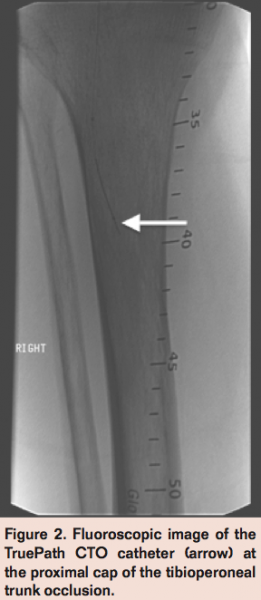

In the setting of CLI with a nonhealing ulcer in the corresponding angiosome, an endovascular intervention of the right TPT occlusion was pursued. A TruePath CTO Device catheter (Boston Scientific) was advanced across the occlusion into the distal peroneal artery (Figure 2). Subsequent angiogram confirmed intraluminal position of the distal wire in the peroneal artery (Figure 3).